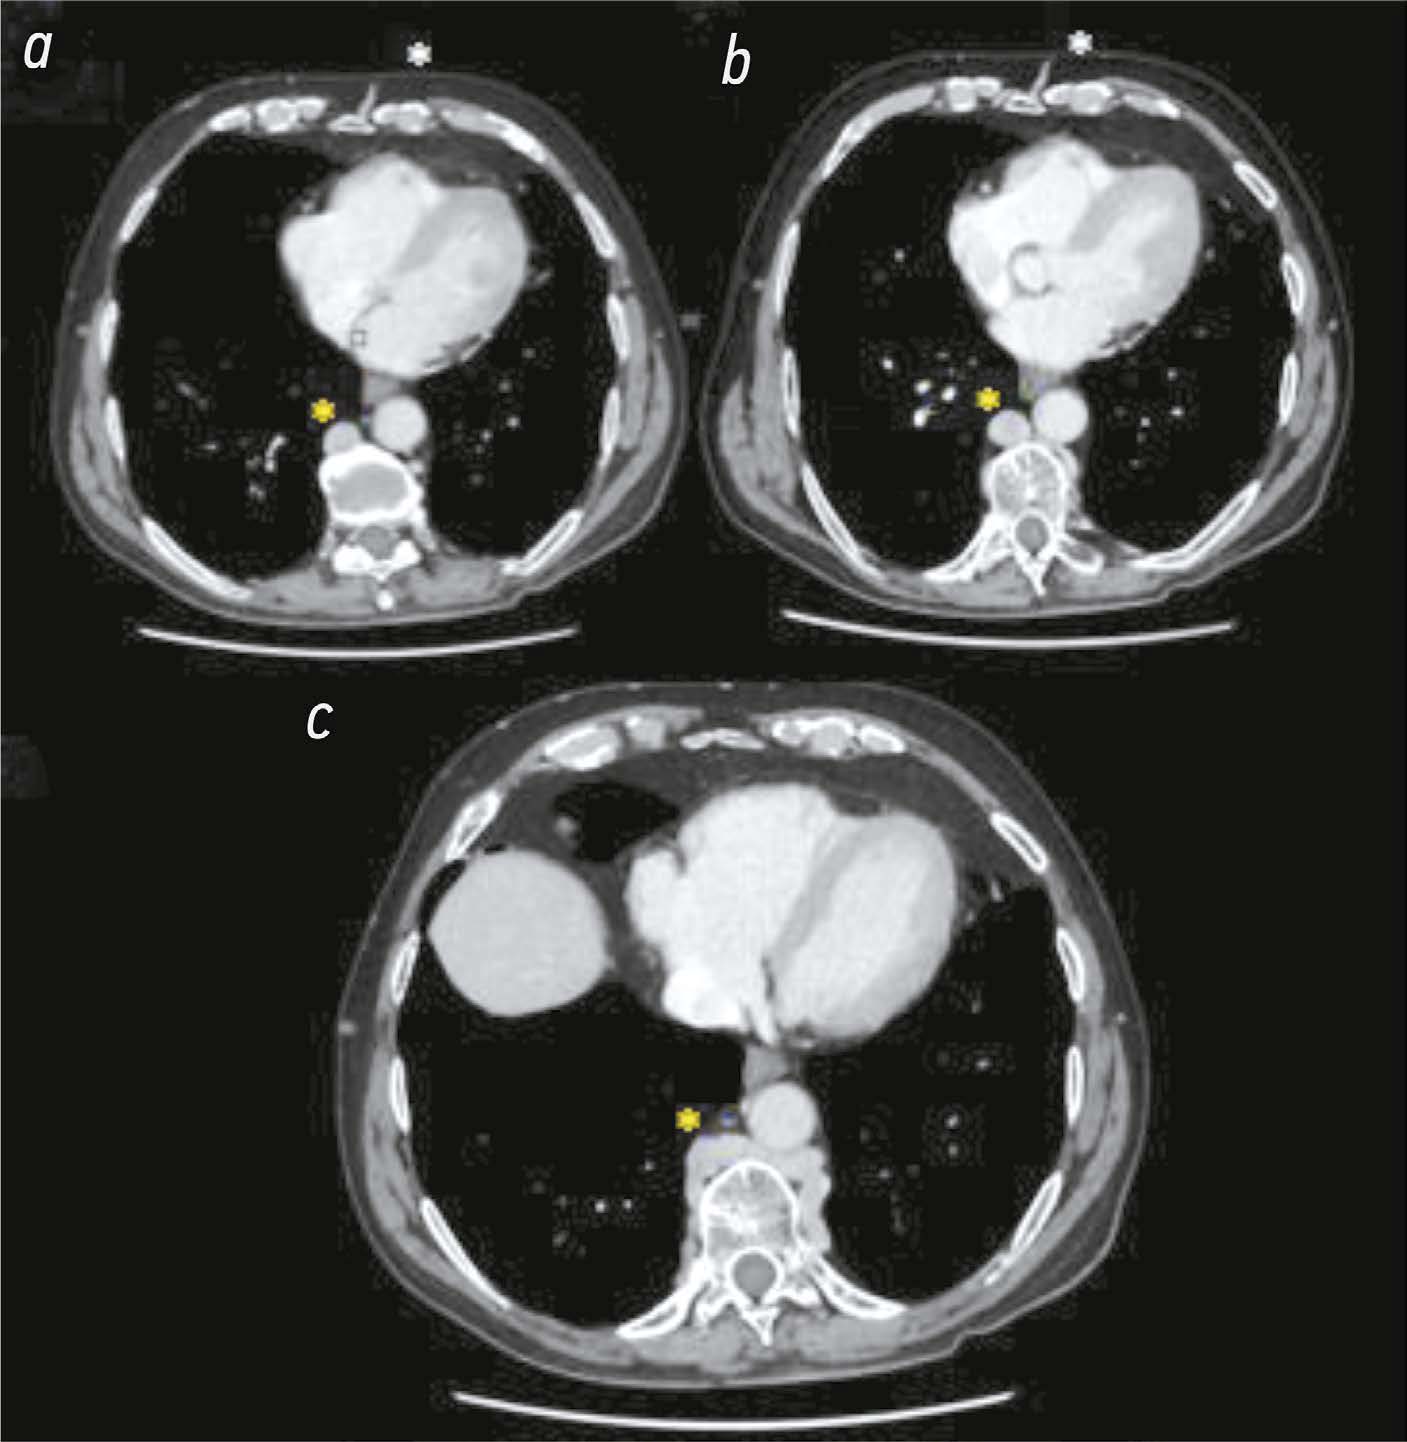

The role of computed tomography in the differential diagnosis of an intracardiac mass of the mitral valve: a case series

The differential diagnosis of an echocardiographically detected intracardiac mass in the mitral annulus can be challenging and usually requires a multimodal approach. This type of lesion is very often associated with subvalvular calcification of the mitral valve. The rare, caseous, variant is the most difficult to diagnose. This case series highlights the clinical significance of computed tomography in detecting and characterizing subvalvular mitral annular calcification when other modalities, particularly echocardiography, are inconclusive. The aim of this article was to raise awareness among specialists of the classic signs of caseous subvalvular calcification of the mitral annulus when visualized with different modalities. Special attention is also given to providing a differential diagnostic series that identifies features that differentiate subvalvular calcification of the mitral annulus from other conditions at this site. Healthcare professionals need to be aware of these mitral valve lesions in order to predict possible associated complications and plan a treatment strategy that may help avoid unnecessary surgical procedures in some cases.

893-901